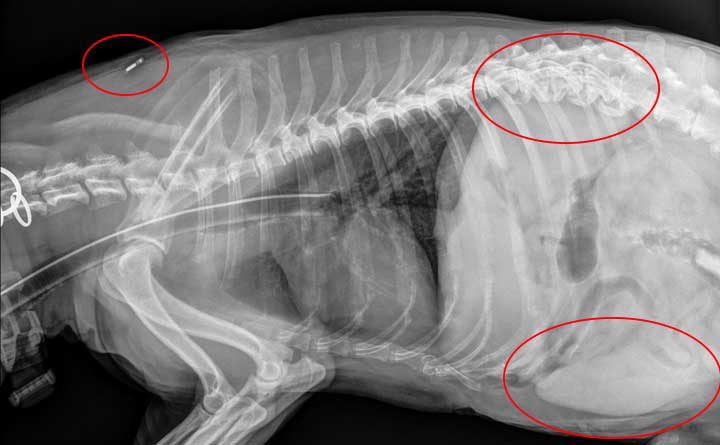

Small dog x ray top, They Ate What Pet X Ray Contest 2012 Winners Veterinary Practice News top

They Ate What Pet X Ray Contest 2012 Winners Veterinary Practice News